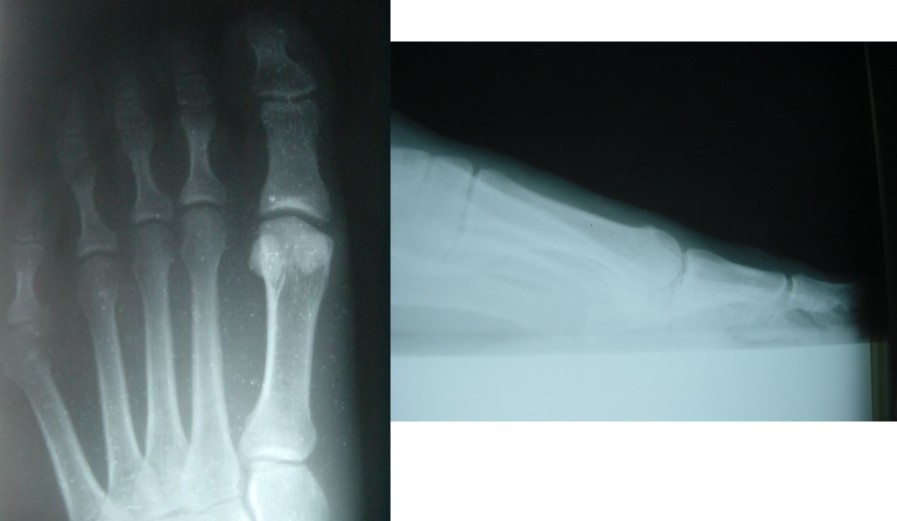

Query: Positional Hallux Limitus

From: Dale M. Smith DPM

Within the last couple of weeks, I've had four 17 to 30-year-old females present with a rectus hallux, no signs of the abductus, complaining of pain of the dorsum medial aspect of the first metatarsel head and exhibiting anywhere from minimal to moderate limitation of motion.

| Positional Hallux Limitus |

In all four cases, lateral weight-bearing, angle and base of gait, x-rays show a significant metatarsus primus elevatus. Some show spurring of the metatarsel head. Maybe I'm reviewing the wrong literature, but I am not finding a plethora of articles suggesting the panacea of procedures for this condition. Any thoughts on the best procedure for a positional hallux limitus.

Dale M. Smith, DPM, Chicago IL